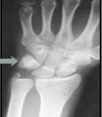

Mano y muñeca – Patología.

¡Buenos días amigos! ¿Cómo estáis? ¿Os están sirviendo las publicaciones? Espero que si. Por cierto, me vais a tener que echar una manita para saber que publicaciones son las que más os gustan, sobretodo en instagram, ya que haré un sorteito cuando llegue a los 500 followers y para eso vais a tener que ayudarme... Leer más →